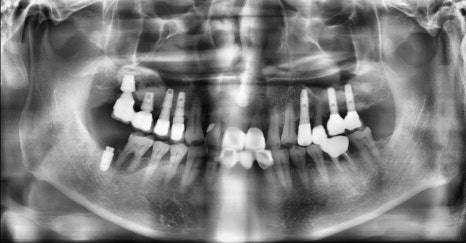

임플란트 2차 수술은 1차 수술 후 3~6개월의 골유착 과정을 거친 후 시행하며, 잇몸뼈와 인공치근(픽스쳐)이 잘 결합하였는지 확인하고 보철물이 올라가기 전에 잇몸의 모양을 잡아주기 위한 과정으로 생각하시면 됩니다. 약간의 잇몸 절개 후 잇몸으로 덮여 있던 임플란트를 노출시키며, 잇몸 회복을 위해 힐링 어버트먼트를 연결하여 치유 기간 동안 잇몸의 모양이 잘 잡히도록 도와주게 됩니다. 1차 수술 시 잇몸뼈의 상태가 좋고 임플란트 픽스쳐의 초기 고정이 잘 나올 경우에는 바로 힐링 어버트먼트를 연결하여 2차 수술이 생략되기도 합니다.

힐링 어버트먼트

수술이라는 단어 때문에 환자분들께서 부담을 느끼실 수 있지만, 2차 수술은 잇몸 절개와 임플란트 구조물 교체라는 비교적 간단한 시술이므로 진료시간도 짧고 별도의 약 처방 없이도 회복이 가능합니다.